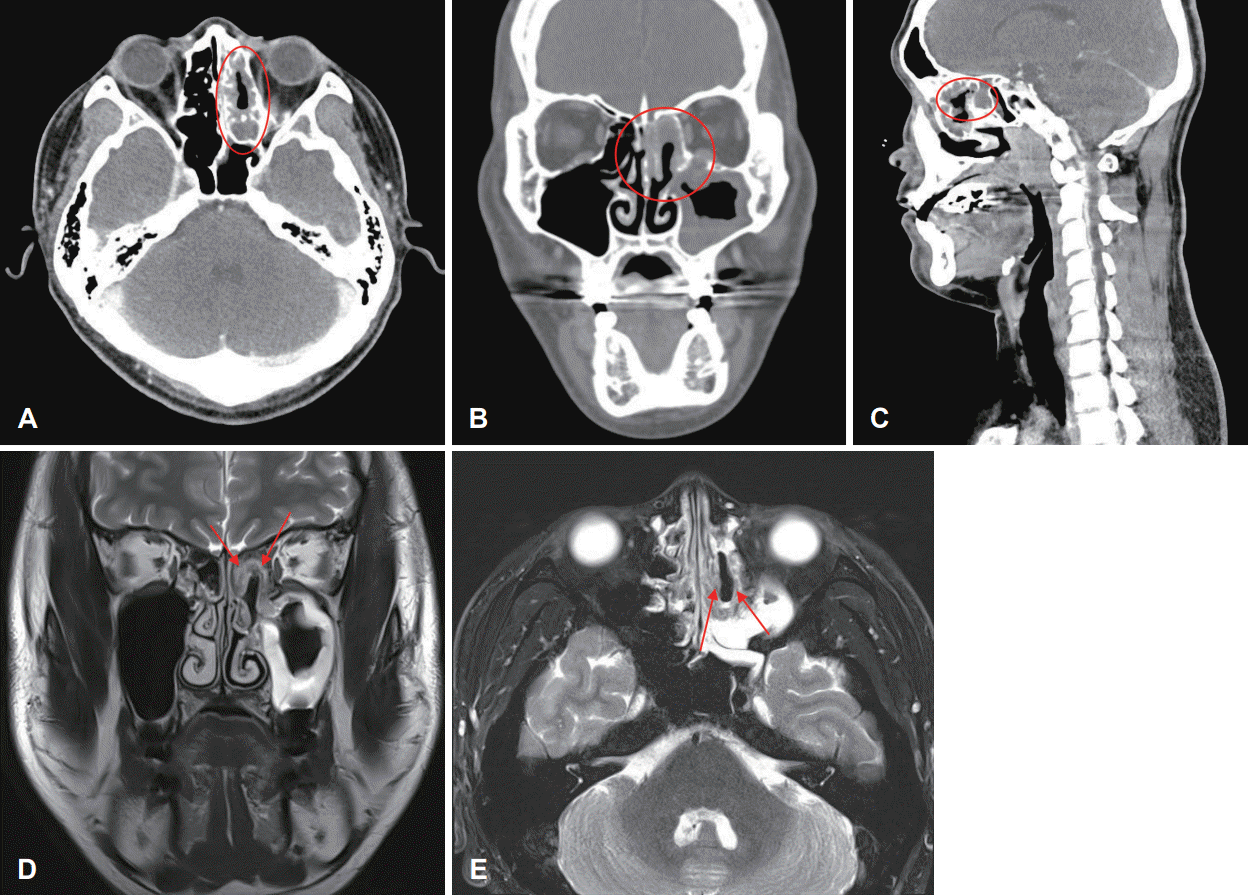

Fig. 1.